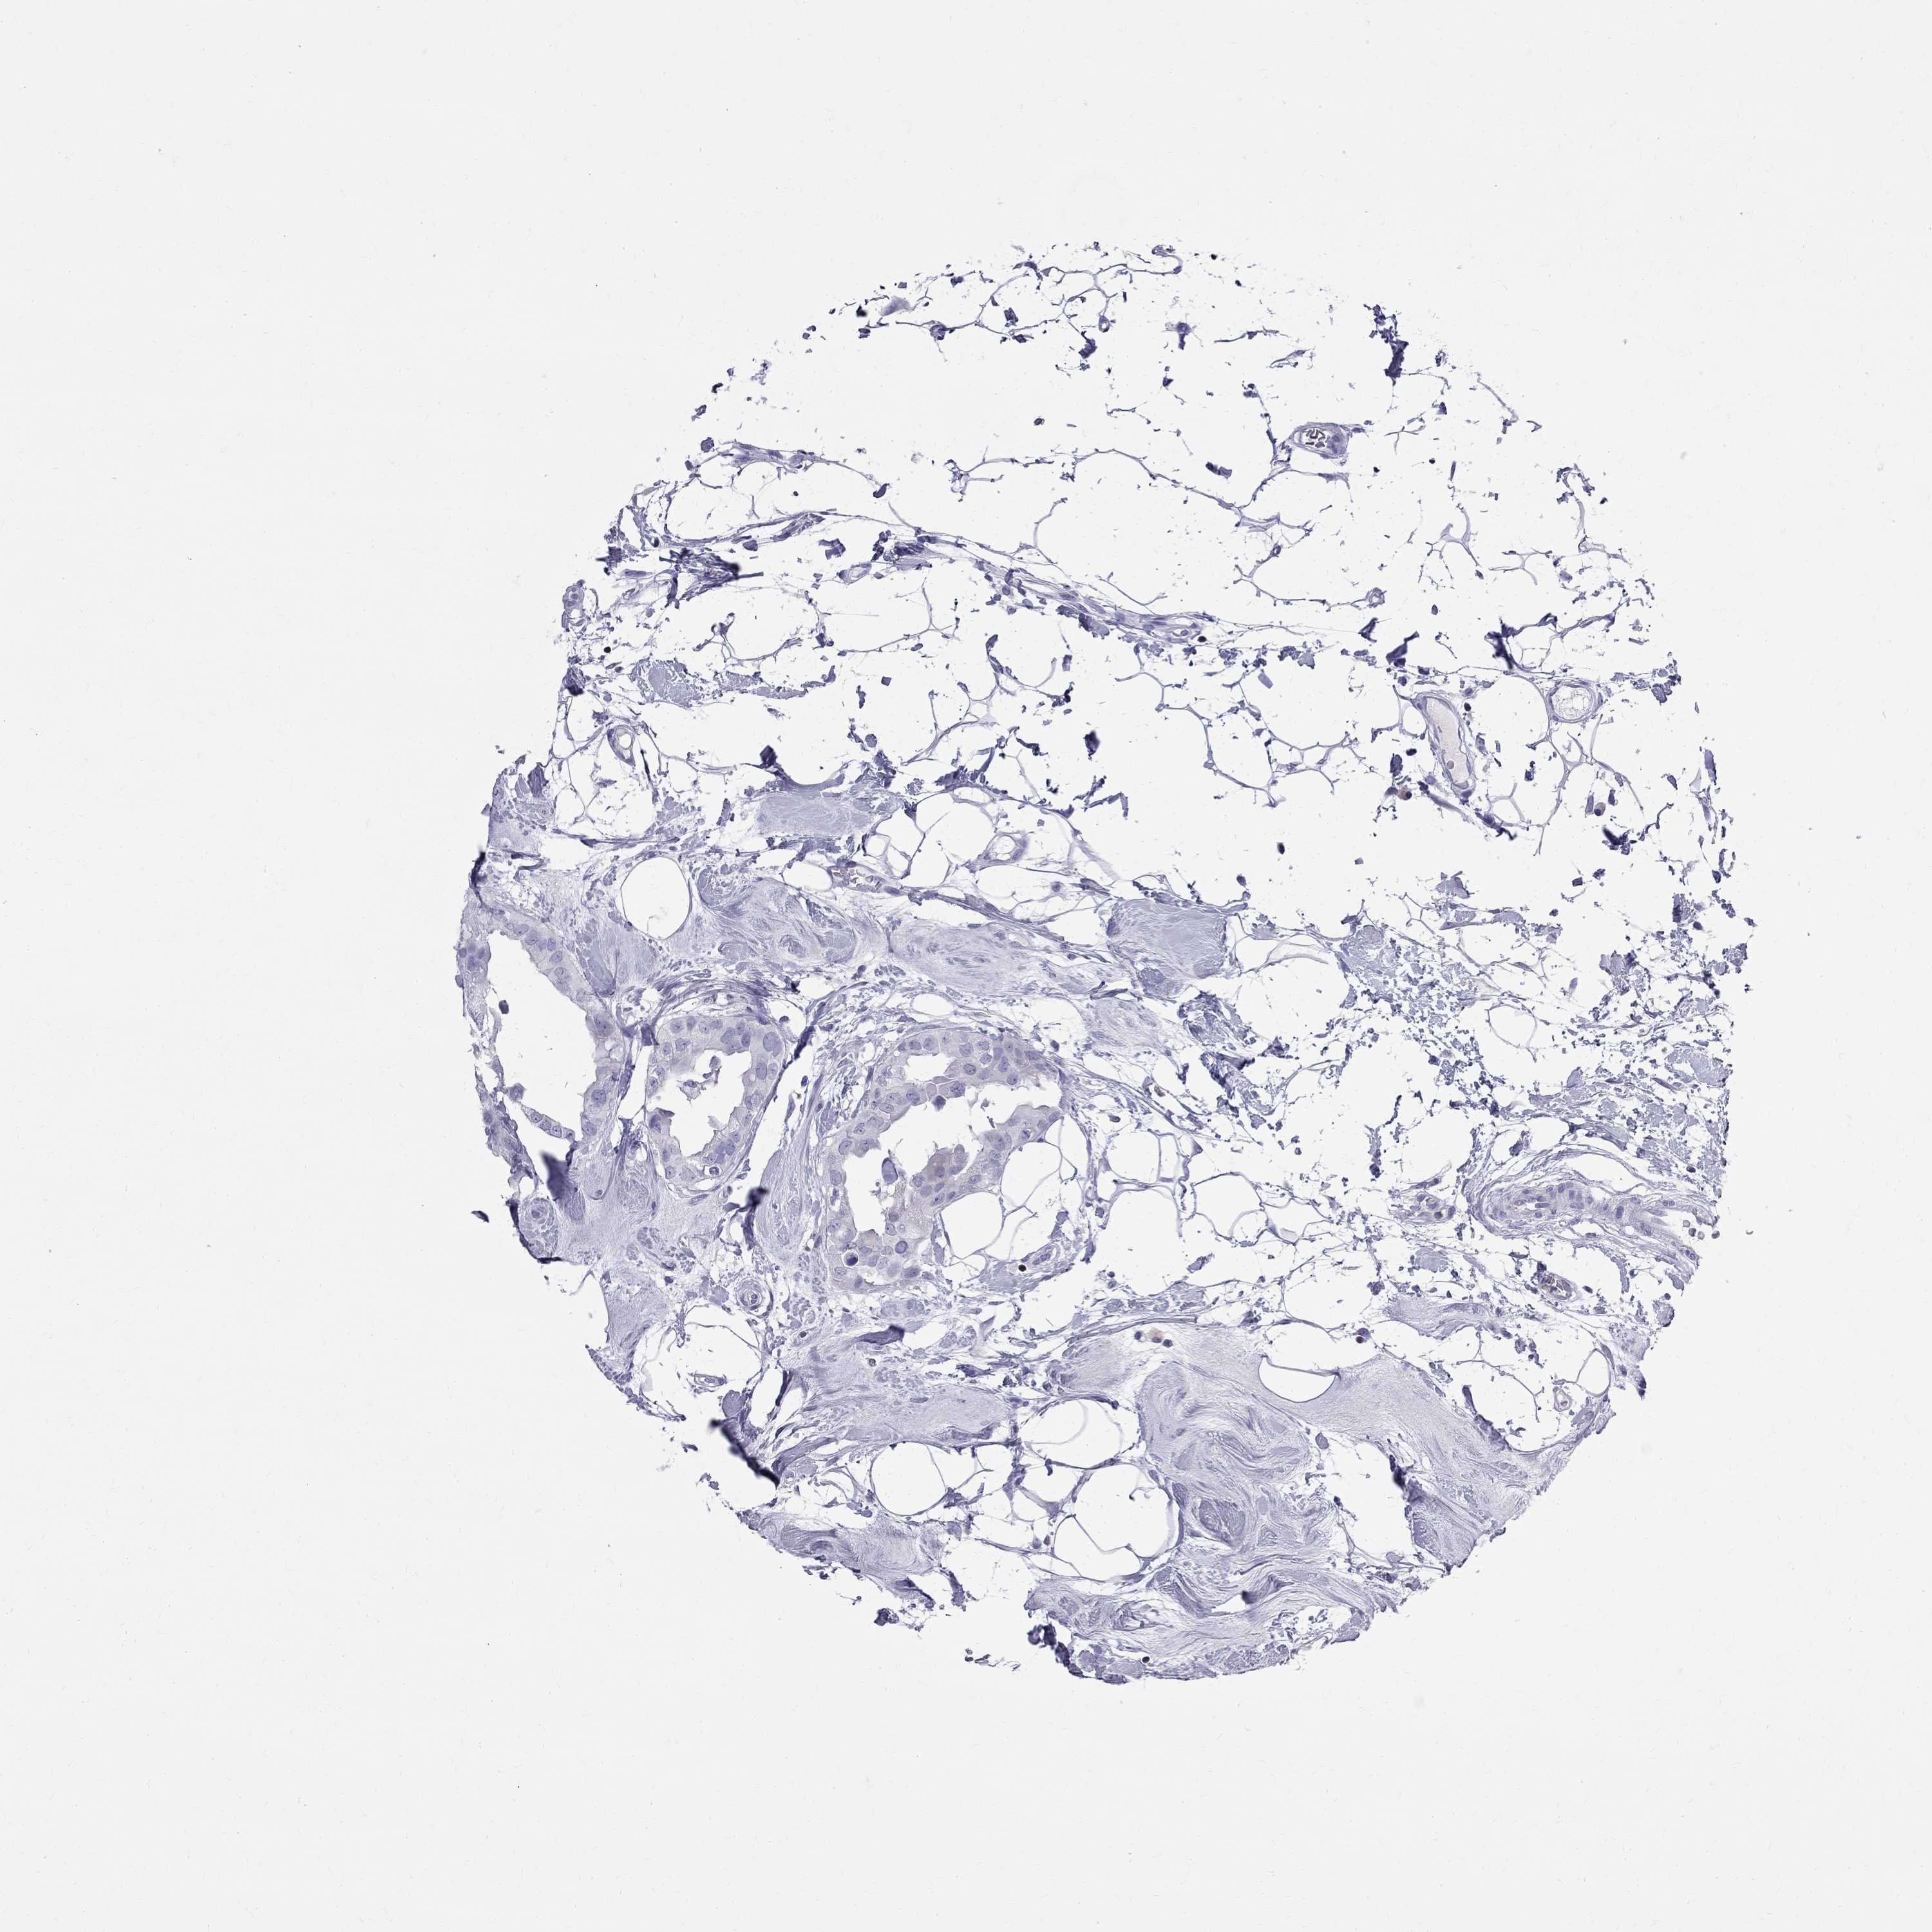

CANCER BREAST CANCER Show tissue menu

Breast cancer

Human cancer